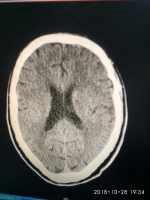

腦梗死患者頭部不適伴高血壓一例 關鍵疾?。?a href="http://m.akellydesign.com/tags/so/高血壓3級-4-1.html" target="_blank">高血壓3級 現(xiàn)病史【一般資料】 男性,64歲,農(nóng)民 【主訴】男性,64歲,農(nóng)民頭部不適2小時入 【現(xiàn)病史】緣于入院前2小時,無明顯誘因出現(xiàn)頭部不適,伴惡心,無嘔吐,伴大汗,當時無頭痛、頭暈,無耳鳴、視物模糊,無發(fā)熱、大汗,無胸悶、胸痛,在家未行特殊治療,急來我院就診。門診查頭顱CT結(jié)果示:左基底節(jié)區(qū)腦腔隙左額葉腔梗。遂以“腦梗死”收入我科,患者自發(fā)病來,精神正常,食欲正常,睡眠及二便均正常。 【既往史】高血壓病病史2年,血壓高達“200/120mHg”,未規(guī)律口服藥物治療,血壓控制不詳,否認糖尿病、慢性支氣管...